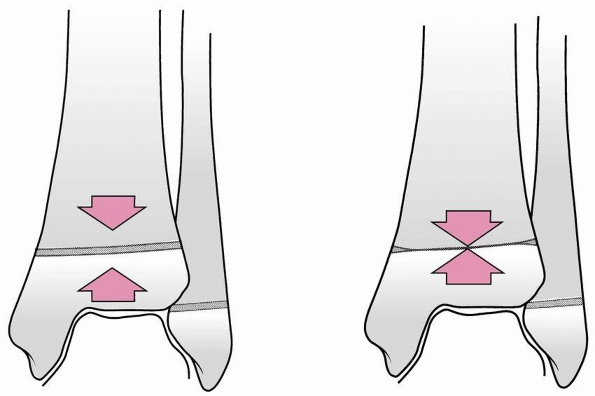

Their original classification (from 1978) consisted of four types in

which the first word refers to the position of the foot at the time of

injury and the second word refers to the force that produces the injury.

Although these are designated differently, the first three have

presumed mechanisms of injury. “Axial compression injury” describes the

mechanism of injury but not the position of the foot. Juvenile Tillaux

and triplane fractures are believed to be caused by external rotation.

![]() |

FIGURE 26-3 Dias-Tachdjian classification of physeal injuries of the distal tibia and fibula.

|